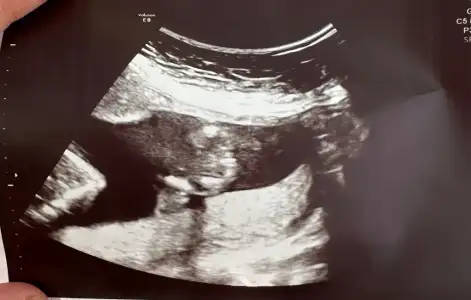

Yorum yaparmısınız. Biri 11hafta 6günlük. Diger 16 haftaKızzzz

kızYorum yaparmısınız. Biri 11hafta 6günlük. Diger 16 hafta

Erkek gibi geldi banaYorum yaparmısınız. Biri 11hafta 6günlük. Diger 16 hafta

Sizinde erkek

Erkek :) givi duruyor ama Allah gönlünüzdekini versinYorum yaparmısınız. Biri 11hafta 6günlük. Diger 16 hafta